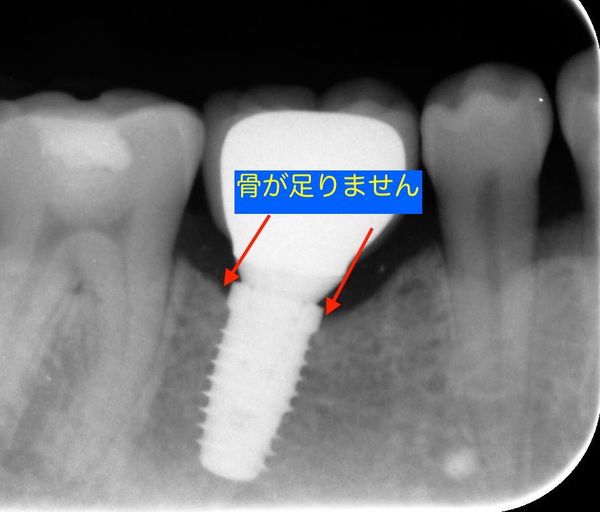

この画像は一年に一回のメンテナンスの際にチェックのために撮影したものです。

インプラントは、むし歯や歯周病などで抜歯した歯にかわって顎骨にインプラントはチタン製の人工歯根を埋めこむ治療です。咬み心地や見た目を回復することができます。インプラントがその機能を十分に果たすためには、埋め込んだ人工歯根インプラントと骨がしっかりと結合することが大切です。骨が十分でないとインプラントと骨がしっかり結合しないため、グラグラしてしまったり、抜け落ちてしまう場合もあります。

通常、きちんと歯科医師が治療をし、患者さんもケアをしてくれればインプラントの周りの骨も増えてきて、安定性は増しますがインプラントの土台となる骨がインプラント設置に耐えられない場合にも「骨を作る治療(骨造成)」も名取歯科医院では行っております。